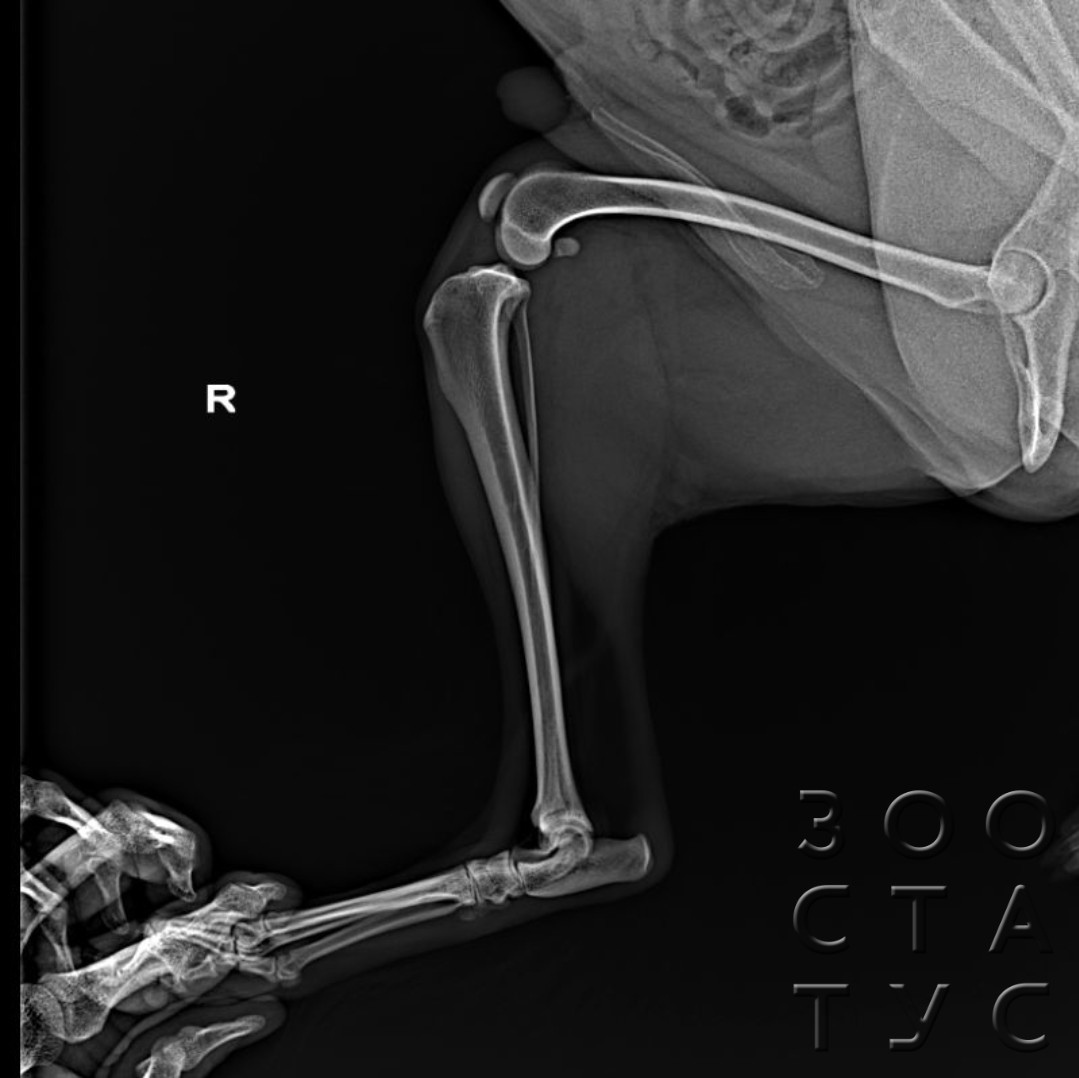

- при хромоте неизвестной этиологии, подозрении на переломы, вывихи, другие травмы, при ортопедических патологиях (болезнь Легга-Кальве-Пертеса, расслаивающем остеохондрите, остеоартрозе, дисплазии и тд);

- рентген лап рекомендуется для всех собак крупных и гигантских пород в возрасте от 4 месяцев для исследования на дисплазию тазобедренных и локтевых суставов;

- тест на дисплазию для РКФ проводится в возрасте 12-18 месяцев - для получения сертификата РКФ об отсутствии дисплазии суставов;

Рентгенография практически всех ортопедических патологий, и все исследования на дисплазию проводятся только под седацией, так как иначе невозможно грамотно расположить собаку для проведения исследования (в частности, при диагностике дисплазии тазобедренного сустава тазовые конечности должны быть параллельны, изображение костей должно быть полностью симметричным, иначе результаты будут недостоверны, такого положения невозможно добиться фиксацией владельцем у неспящего животного, даже если собака абсолютно спокойна). Седация необходима и агрессивным или напуганным животным, жесткие способы фиксации могут нанести гораздо больше вреда их здоровью, чем медикаментозный сон.

Для получения рентген-снимка на дисплазию для РКФ исследование собаки обязательно должно проводиться под седацией.